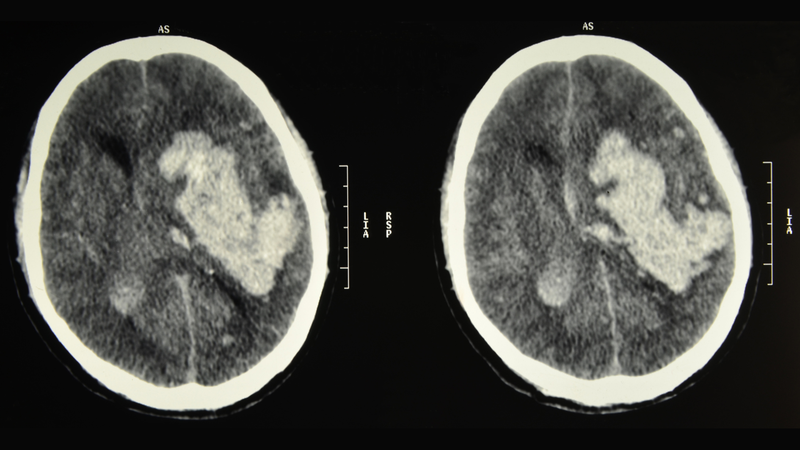

Điều đáng chú ý hơn nữa chính là trong những trẻ bị xuất huyết do thiếu vitamin K thì có đến ½ trẻ có thể bị xuất huyết não, não úng thủy hay tổn thương não vĩnh viễn. Những trường hợp khác thì xuất hiện xuất huyết ở các bộ phận khác của cơ thể. Có không ít trẻ phải truyền máu và bắt buộc phải được phẫu thuật.